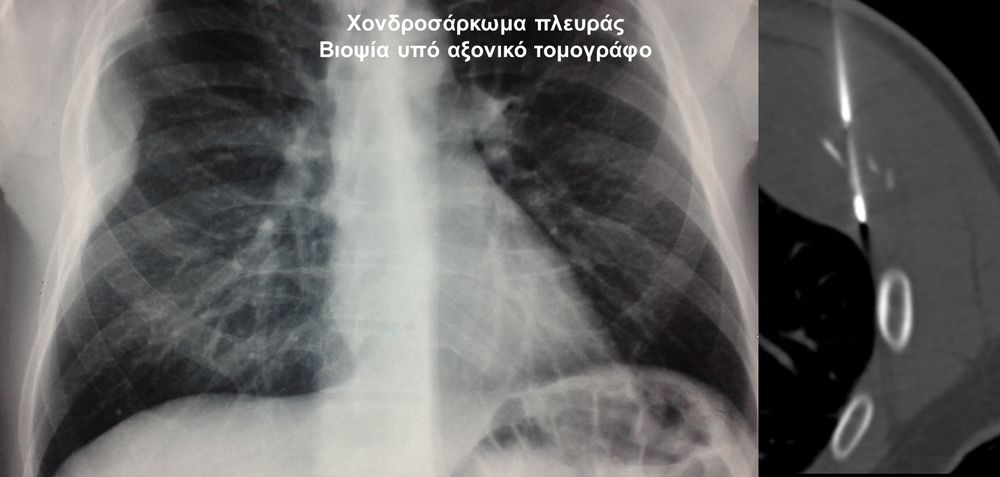

Η οστική βιοψία και η βιοψία όγκων μαλακών μορίων χρησιμοποιείται για την ιστολογική διάγνωση αλλοιώσεων (καλοήθων - κακοήθων / πρωτοπαθών ή μεταστατικών) ή για τη λήψη υλικού προς καλλιέργεια ώστε να αναδειχθεί το μικρόβιο που προκαλεί τη λοίμωξη του μυοσκελετικού συστηματος (πχ σπονδυλοδισκίτιδα). Η βιοψία υπό συνεχή απεικονιστική καθοδήγηση συμβάλλει στην υψηλή ακρίβεια τοποθέτησης της βελόνης εντός της βλάβης με ασφαλή προσπέλαση. Η χρήση σύγχρονων ομοαξονικών συστημάτων βιοψίας (coaxialtechnique) επιτρέπει την λήψη πολλαπλών δειγμάτων με μια μόνο παρακέντηση.